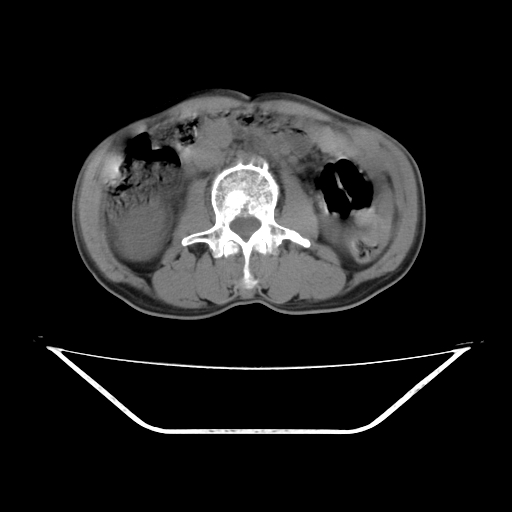

平扫

考虑右肾盂癌,肾动脉受侵,右肾功能减退,右肾盂输尿管积水,管壁增厚,考虑种植转移,应该把下面扫完的

考虑右侧肾盂癌。右侧输尿管扩张未扫描完。

右肾盂癌,肾动脉受侵,右肾盂输尿管积水,管壁增厚,考虑种植转移

右肾盂移行细胞癌并右输尿管中段转移.肾积水.

1.右侧肾盂癌伴肾盂积水。

2.肾脏功能减退,原因有:(1)肾动脉受侵。(2)肾静脉受侵(3)肾积水,等。本例,肾动脉显影较好,但受压明显;肾静脉无明显显示,受压或静脉癌栓,下腔静脉腔内未见明显充盈缺损。

3.右侧上段输尿管扩张,原因:(1)积水所致;(2)种植。